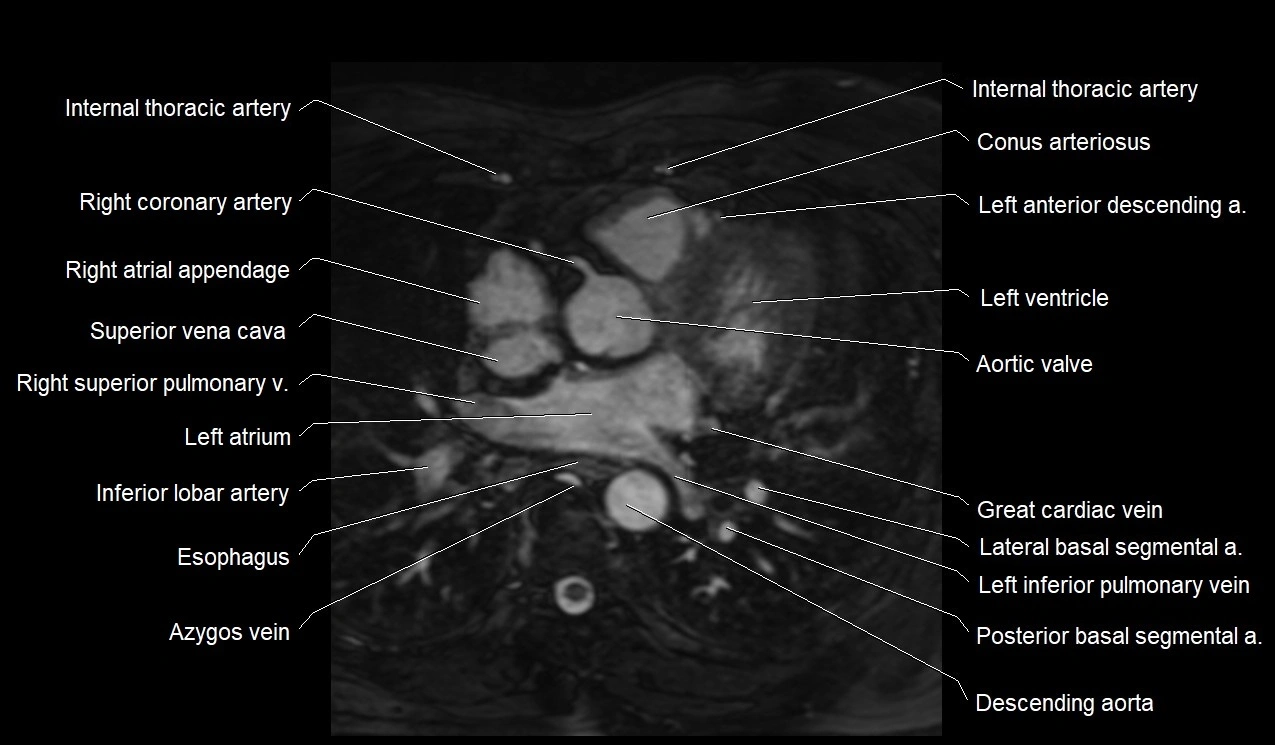

CT images